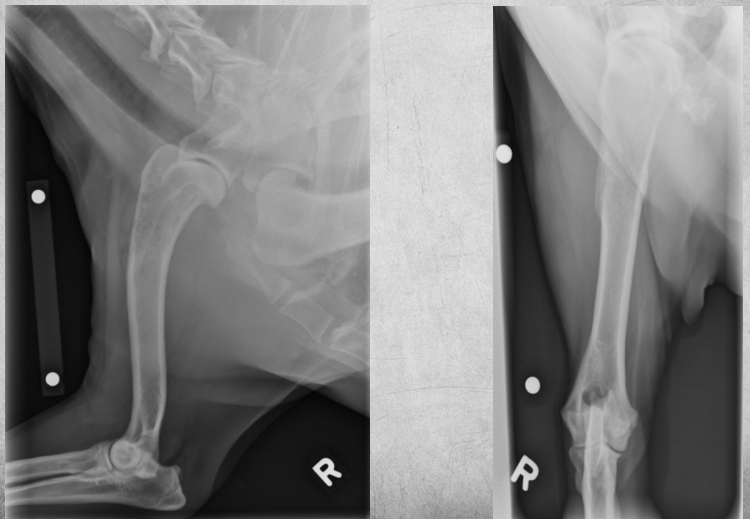

3

12 years old female neutered Labrador

Sudden onset lameness after ball game

Front right leg

Permeative lysis of the cranial and proximal diaphysis and metaphysis of the humerus.

Smooth periosteal reaction is visible on the caudal, medial, and lateral aspects of the humerus.

Diagnosis: Sarcoma, most likely osteosarcoma.